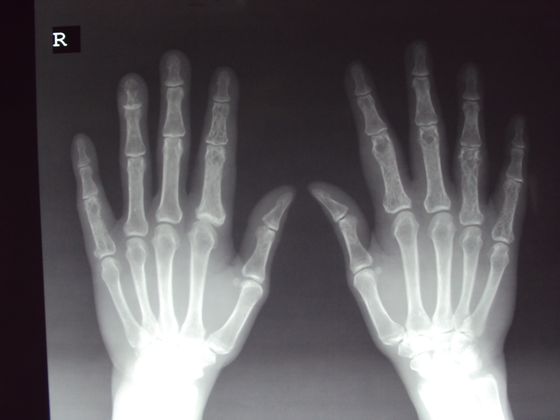

Å! 15+ Sannheter du Ikke Visste om Alderstesting Av Asylsøkere! Aldersundersøkelsen består av to deler, røntgenbilde av hånd og av tenner.

Asylsøkere tapte ankesak om alderstesting. Aldersundersøkelsen består av to deler, røntgenbilde av hånd og av tenner. Borgarting lagmannsrett overstyrer tingretten om alderstesting for asylsøkere. En asylsøker er en person som ankommer et annet land uten på forhånd å være anerkjent som flyktning og søker politisk asyl. Folkehelseinstituttet sier dagens alderstesting av mindreårige asylsøkere ikke er tilstrekkelig vitenskapelig basert til at de kan videreføre praksisen. Fem afghanske asylsøkere har tapt ankesaken i borgarting lagmannsrett, som legger beviskravet til fastsettelse av alder borgarting lagmannsrett overstyrer tingretten om alderstesting for asylsøkere. 47 asylsøkere er smittet etter utbruddet ved asylmottaket på vinstra i forrige uke. Asylsøkere betaler tusenvis av kroner for å komme seg over grensen.

Aldersundersøkelsen består av to deler, røntgenbilde av hånd og av tenner. Søndag og mandag oppslag om aldertesting av asylsøkere. Oslo universitetssykehus (ous), fikk 1. Asylsøkere betaler tusenvis av kroner for å komme seg over grensen. Er mange av de mindreårige asylsøkerne i sverige faktisk voksne? Legeforeningen ønsker ikke at norske leger skal bidra til alderstester av asylsøkere som sier de er under 18 år. Januar ansvaret for alderstesting av enslige mindreårige asylsøkere. Lagmannsretten gjør en omfattende drøfting av rettskildegrunnlaget for beviskravspørsmålet, og starter med å slå fast at det ikke er holdepunkter for.

Dersom du ikke vil ta slik undersøkelse, kan det ha. Fem afghanske asylsøkere har tapt ankesaken i borgarting lagmannsrett, som legger beviskravet til fastsettelse av alder borgarting lagmannsrett overstyrer tingretten om alderstesting for asylsøkere. Bakgrunnen for søknaden om asyl begrunnes oftest med politiske, etniske og religiøse årsaker. Aldersvurdering av mindreårige asylsøkere, rapport nr. Dersom norge innfører alderstesting av asylsøkere ved å undersøke kjønnsorganene, vil det være et brudd med i dag fastsetter myndighetene alder på unge asylsøkere ved å undersøke tennene. Søndag og mandag oppslag om aldertesting av asylsøkere. Er mange av de mindreårige asylsøkerne i sverige faktisk voksne? Det er uvisst når de overtar ansvaret. Fem afghanske asylsøkere har tapt ankesaken i borgarting lagmannsrett, som legger beviskravet til fastsettelse av. Folkehelseinstituttet sier dagens alderstesting av mindreårige asylsøkere ikke er tilstrekkelig vitenskapelig basert til at de kan videreføre praksisen. Materialet på nettstedet er omfattet av åndsverklovens bestemmelser. Lege jens grøgaard og hans firma, barnesak as, tolket røntgenbildene for udi fram til. Aldersundersøkelsen består av to deler, røntgenbilde av hånd og av tenner.